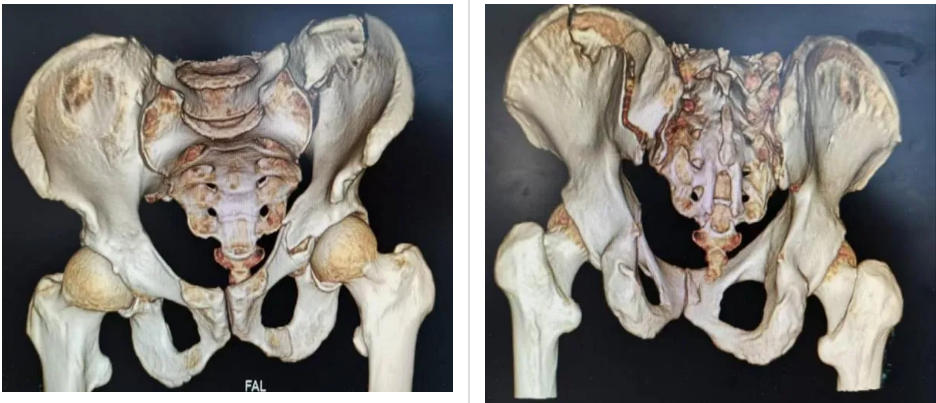

患者是一名高空坠落导致骨盆、髋臼骨折的老年男性。入院后完善术前检查,结合骨盆三维CT扫描诊断为骨盆骨折合并左侧髋臼骨折及骶髂关节脱位(分型为TileC1.3)。由于骨盆内分布许多重要脏器以及血管神经,对于手术操作精准度要求极高,否则容易伤及周围神经血管或盆腔脏器。为最大程度减少手术创伤及出血,骨关节外科冷明昊主任经过充分考虑,决定在新型“HoloSight智能可视化系统”机器人的辅助下,为患者实施微创手术。

术中,在医院手术室的大力支持下,主刀医生冷明昊主任首先将定位追踪器安置在患者髂棘合适位置上,再结合CT透视所得将患者骨盆影像资料导入手术机器人中,通过机器人自动化算法将影像图片与骨盆实体情况进行精准配对,并在显示器上规划好骶髂螺钉、前柱螺钉位置、长度以及角度,随后准确无误地将骶髂螺钉、前柱螺钉植入患者体内。手术全程通过机器人监视下调整角度,快速定位、精准植入、切口仅用1cm,术中出血量约10ml,手术安全顺利结束。术后,患者恢复良好,目前可在床上自行翻身、端坐等活动。